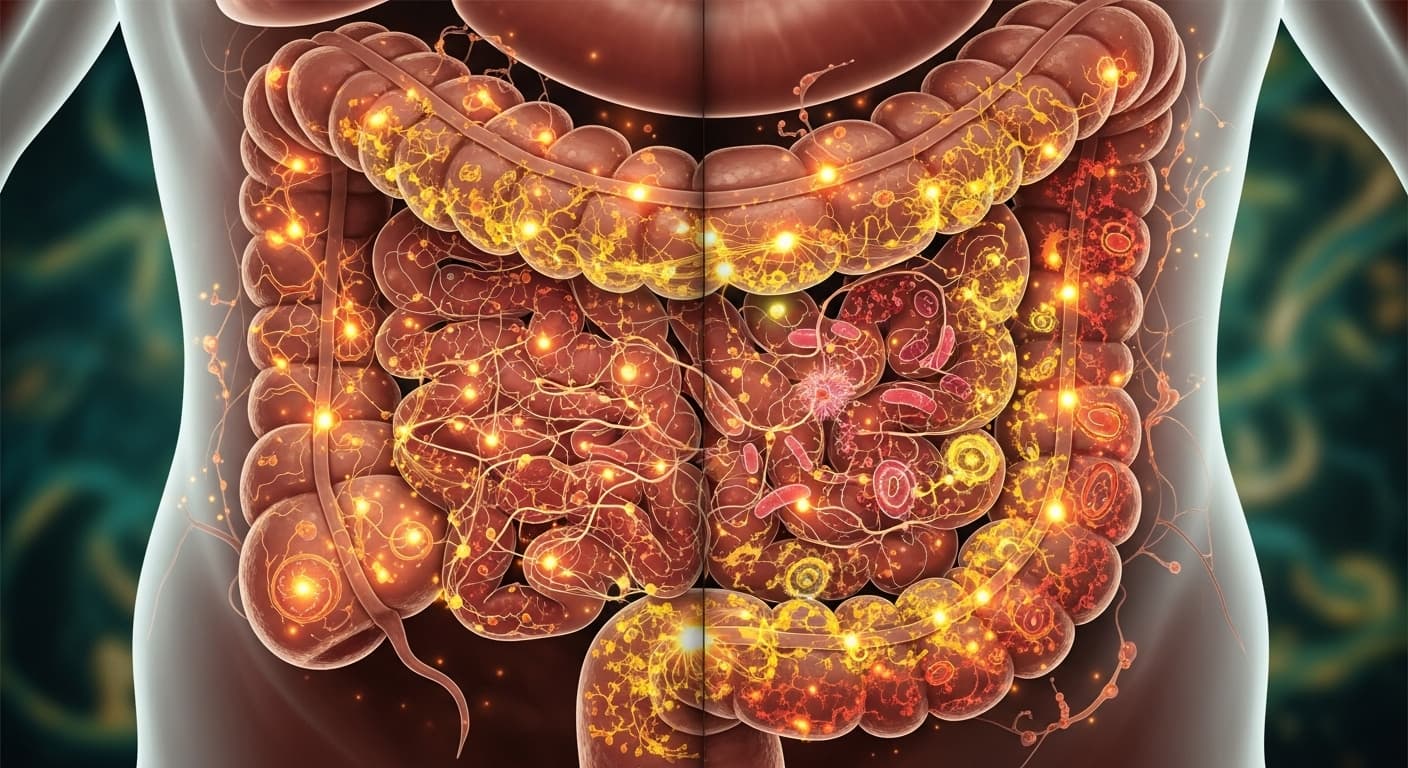

"갑자기 배가 살살 아프더니, 으윽... 화장실로 달려가 하루 종일 들락날락, 온몸에 힘이 쭉 빠지고 머리까지 지끈거리는 경험, 한 번쯤 해보셨죠? 찬 바람 불기 시작하면 꼭 찾아오는 불청객, 바로 바이러스 장염인데요. 오늘은 그 지긋지긋한 장염의 근본적인 이야기부터 현명한 대처법까지, 제가 따뜻하게 풀어드릴게요."

"갑자기 배가 살살 아프더니, 으윽... 화장실로 달려가 하루 종일 들락날락, 온몸에 힘이 쭉 빠지고 머리까지 지끈거리는 경험, 한 번쯤 해보셨죠? 찬 바람 불기 시작하면 꼭 찾아오는 불청객, 바로 바이러스 장염인데요. 오늘은 그 지긋지긋한 장염의 근본적인 이야기부터 현명한 대처법까지, 제가 따뜻하게 풀어드릴게요."

물처럼 쏟아지는 설사에 몸은 빠르게 탈수됩니다. 이온 음료나 보리차, 끓인 물을 미지근하게 해서 조금씩, 그리고 자주 마셔 몸에 수분을 보충해주세요. 한 번에 많이 마시면 오히려 위장을 자극할 수 있으니 주의하세요. 2. 부드럽고 따뜻한 음식으로 위장 달래기: 기름지고 자극적인 음식은 절대 금물이에요. 흰죽, 미음처럼 부드럽고 소화하기 쉬운 음식을 따뜻하게 섭취해 위장에 부담을 주지 않고 회복을 돕는 것이 중요합니다. 너무 굶기보다는 소량이라도 부드러운 음식을 드시는 게 좋아요.